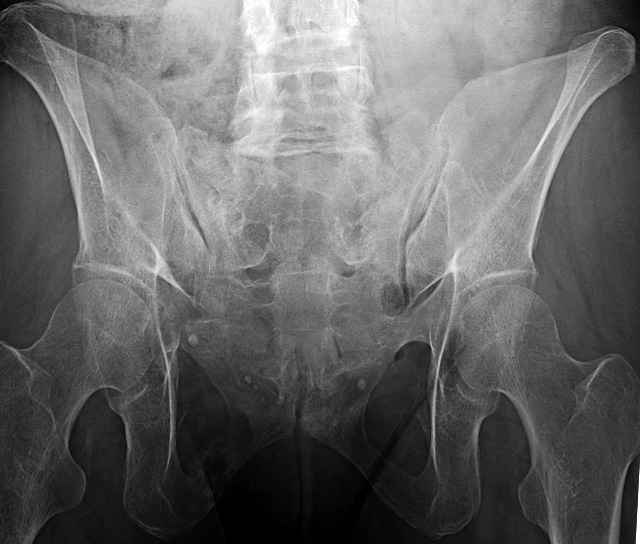

Initial Films

?Instability on Exam - Limited by Pain

NonOp Initial Mgmt